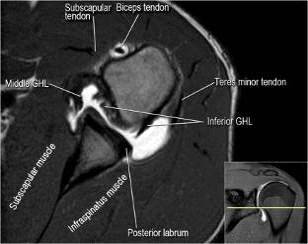

Рис. 5 Нормальная анатомия плечевого сустава в аксиальной проекции

В аксиальной проекции определяются повреждения костей и хрящей,

образующих плечевой сустав